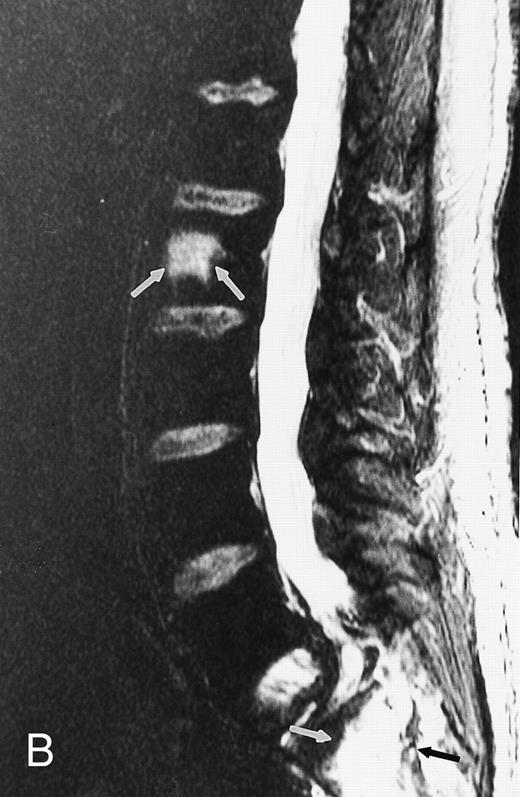

T1-weighted (500/11, TR/TE) sagittal MR images of the lumbosacral spine in a 45-year-old woman before (A) and 40 days after (B) bone marrow transplantation for multiple myeloma. There is a diffuse MR pattern of marrow involvement in (A) (bone marrow plasma cells, 50%; monoclonal protein, 6.0 g/dL). On the posttreatment image, there is definite reinstitution of fatty marrow in the spine and, in particular, around the basivertebral veins, in keeping with partial response to treatment (bone marrow plasma cells, 0.5%; monoclonal protein, 1.6 g/dL).

During the first posttransplantation days, marrow necrosis is seen as a decrease in the signal intensity of the marrow on T1-weighted images and as increased brightness on T2-weighted images. Within 3 months from bone marrow transplantation, a characteristic band pattern appears on T1-weighted MR images of the spine.90 This band pattern consists of a peripheral zone of dark signal and a central zone of bright signal. At histologic examination, the peripheral zone corresponded to repopulating hematopoietic marrow and the central zone to marrow fat.90 Stevens et al90 observed the band pattern in all but 1 of 15 patients within 90 days after bone marrow transplantation and up to a follow-up of 14 months. In 1 patient with relapse of disease, the band pattern evolved to a more homogeneous appearance of the marrow. In our experience, the band pattern gradually evolves into a homogeneous appearance of the marrow after successful bone marrow transplantation.